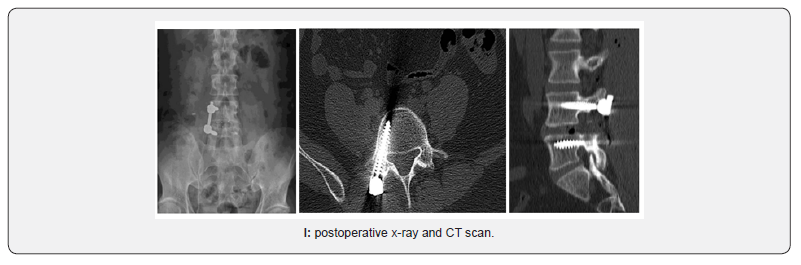

With the patient in prone position under general anesthesia, use of intensified fluoroscopy images with C-arm, surgical approachwas executed on the most symptomatic side. Incision of approx. 3 cm was performed, using micro-discectomy separators. It is started by placing transpedicular screws of the affected segment and a TLIF separator is used, subsequently a lamina and articular facet osteotomy and medial facetectomy was completed. The Kambi’s triangle is located, the medial and lateral root is retracted, preparation was performed, and bone graft was delivered in the lumbar intersomatic space. A rectangular bulletnose cage was implanted. To conclude, unilateral transpedicular screws were placed on the rod. Figure 1.

Clinical outcomes were evaluated pre- and postoperative using the ODI, visual analogue scale (VAS) for leg and back pain, patients must complete a minimum of 2 years of follow-up. Interbody fusion was analyzed on radiography and on a CT scan.

ODI and VAS were significantly enhanced (p < 0.05) at the end of the follow-up. The mean follow-up was 38 months (range 25—42). There was positive progress from the first 3 months, which was increasing in the subsequent months (Table 2). VAS leg pain improved in all patients. As well as low back pain was improved (p<0.01). The average hospital time was 3 days, no trans-operative complications, infections or dural tear were reported. All patients at the next day started walking and immediately physical therapy and rehabilitation. Drainage was routinely placed. No patient needed transfusion. At the 3-year follow-up the fusion rate was 95% on radiographic analysis and was 93% on CT scan analysis. A loosening of the screw was reported, without pain in one patient treated with rest and physical therapy, with good evolution. No infections were reported. There was a considerable decrease in the use of analgesics in the first 3 months.